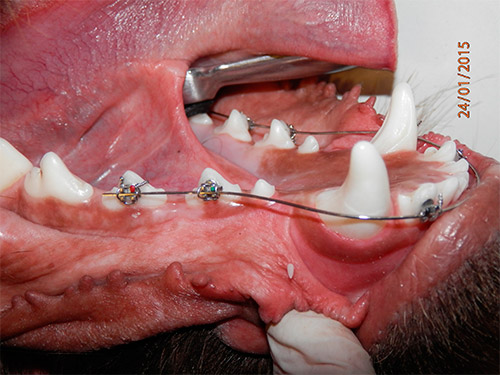

В нашей клинике систематизирована система оценки болезней ротовой полости. Таких как – пародонтит , гингивит. Разработана методика чистки зубного камня которая позволяет в два раза удлинить период между чистками . Более совершенная техника удаления больных зубов которая позволяет профилактировать развитие пародонтита и рецессии рядом стоящих зубов. Появилась методика лечения зубов с парадонтитом. Особенно хочется выделить успешные методики лечения ЛПСГК (Лимфацитарно плазмоцитарный стоматогингивит котов). Появилась возможность косметической коррекции прикуса ротовой полости.